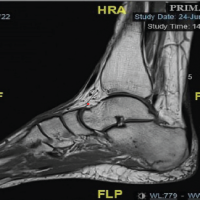

In the left foot, magnetic resonance imaging (MRI) revealed a fracture at the base of the first metatarsal with bone marrow edema extending from the base into the shaft, consistent with a stress fracture (Fig. 2). In the right foot, MRI showed a fracture of the dorsal base of the first metatarsal with associated bone marrow edema. The radiologist also noted bone bruising of the first cuneiform posteriorly (Fig. 3). It is possible to appreciate initial radiological sign of osteoarthritis of the fist metatarsal-phalangeal joint (subchondral sclerosis and narrowing of the joint space) The patient was treated with bilateral post-operative rocker sole shoes that she has worn for 6 weeks. Then, she transitioned to rigid sole shoes. She was allowed to walk with free weight-bearing. She was also instructed to use cryotherapy and prescribed analgesics as needed. Pulsed electromagnetic fields (PEF) were also prescribed; the device used was BIOSTIM (IGEA, Carpi, Italy), which generates pulses 1.3 milliseconds in duration, with a frequency of 75 Hz. She underwent PEF for 8 h per day for 40 days. Sports activities were restricted for 1 more month. After an overall period of 10 weeks, a new MRI showed a complete resolution of the previous finding; at the clinical evaluation, no symptoms were recorded. The patient returned to sport with no limitation. No specific shoes were suggested. At the last follow-up, 1 year after the injury, she reported no problem, and she reports that she has returned to running and practicing sport at the same level she had before the fractures. At the last follow-up, she was given the American Orthopaedic Foot and Ankle Society Hallux Metatarsophalangeal-Interphalangeal questionnaire [19], and the scores obtained were 93 for both sides underlying an excellent resumption of patients’ daily life activities [19].